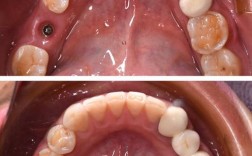

- 粘接托槽: 这是“上钢牙”的过程,医生在牙齿表面酸蚀、涂粘接剂,然后将托槽精确地粘在预定位置,这个过程通常需要1-2小时。